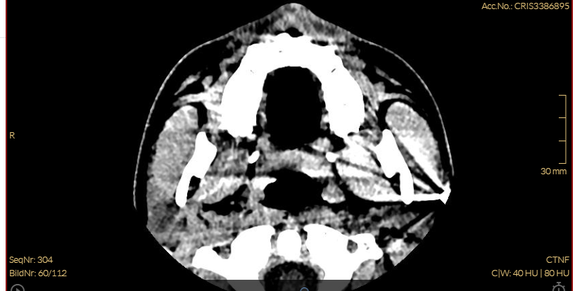

Der zuständige Arzt ordnet eine Computertomografie (CT) an, erkennt darauf aber nichts Auffälliges. «Man sagte mir, es handelt sich bei meiner Verletzung um eine Prellung.»

Spital sieht Kugel auf ursprünglichem CT

Die Ärzte hätten die Kugel also auch auf dem ersten CT sehen müssen.

Immerhin: Nachdem die Kugel endlich entdeckt war, geht es schnell. Der behandelnde Arzt des Spitals überweist Jasper sofort an einen Spezialisten, der die Kugel chirurgisch in der Klinik Bethanien entfernen soll.